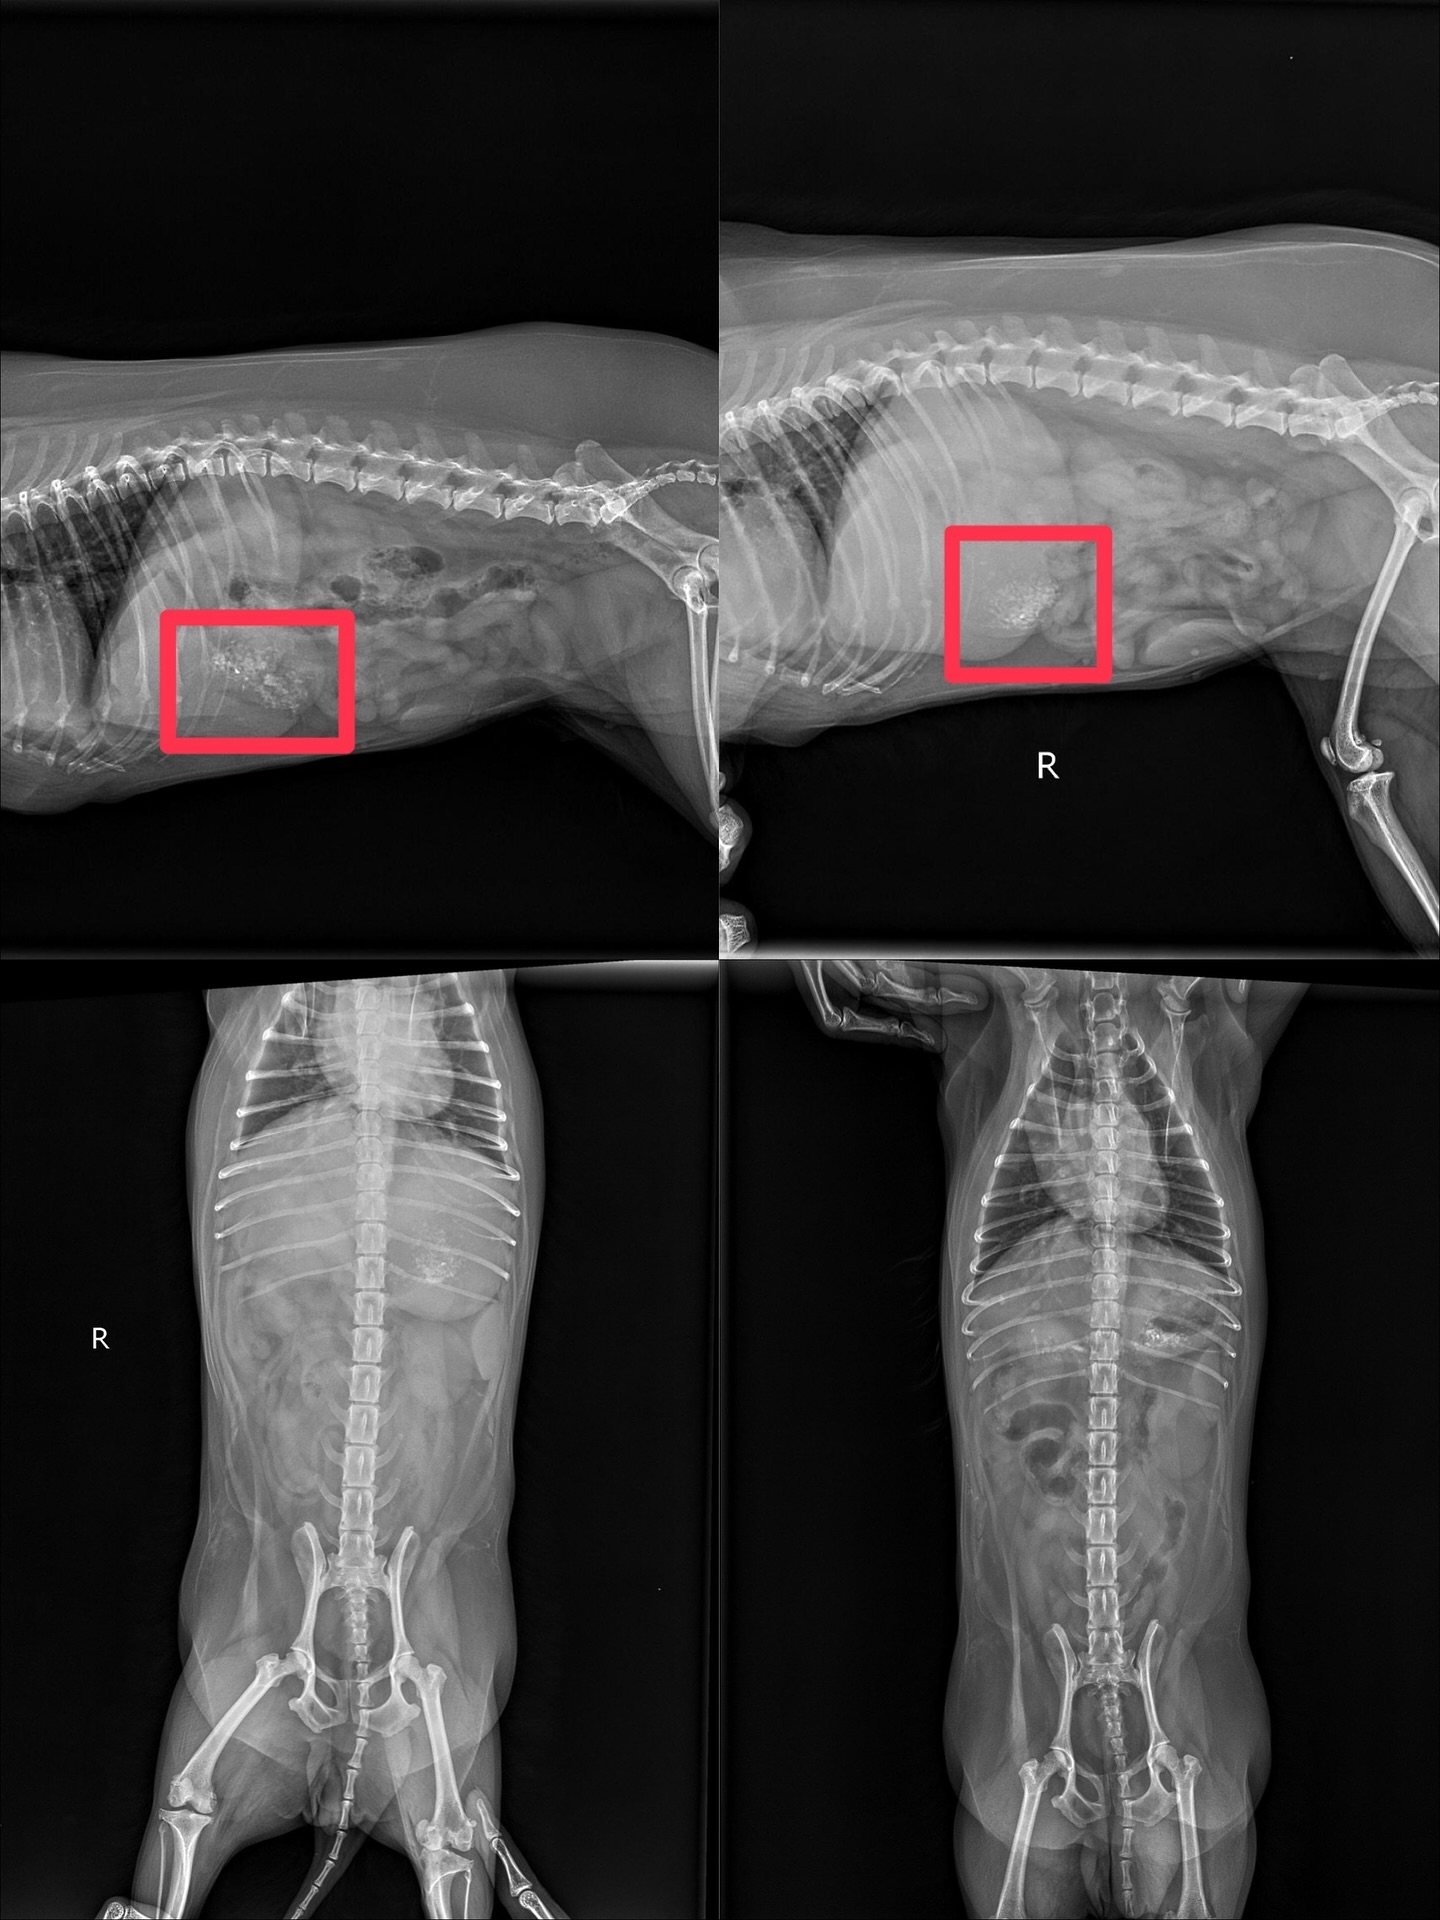

ได้ X-Ray, ส่องกล่อง และอัลตร้าซาวด์ พบว่ามีเศษที่มีลักษณะแข็งคล้ายกระดูกและไม้

กระจายอยู่เต็มกระเพาะอาหาร ลักษณะมีทั้งสีขาวแหลมเป็นก้อนแข็ง คล้ายกระดูก ปูน,

สีดำและสีน้ำตาลคล้ายเศษไม้ คุณหมอได้ทำการล้างท้อง แต่เศษดังกล่าว

ยังคงติดค้างอยู่ในบริเวณท้องตอนนี้แพทย์กำลังดำเนินการรักษาอย่างต่อเนื่อง